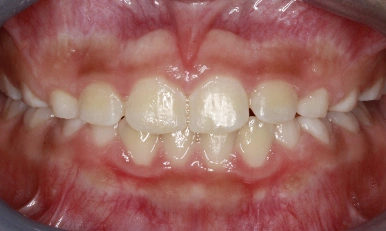

Patient Results